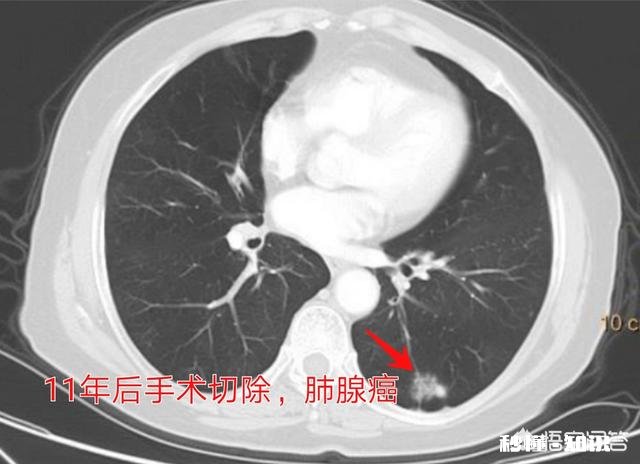

反之,像甲状腺癌、前列腺癌、高分化的肺腺癌等,比较温良,生存期很长 , 甚至不影响寿命 。

像这位女性患者,体检发现左下肺高危肺结节,以磨玻璃为主 , 随访观察了11年,最后一次发现有增大趋势才手术切除,病理是肺腺癌 。

这是名副其实的“懒癌”!

如果所有的癌症都是这种懒癌,就好了!